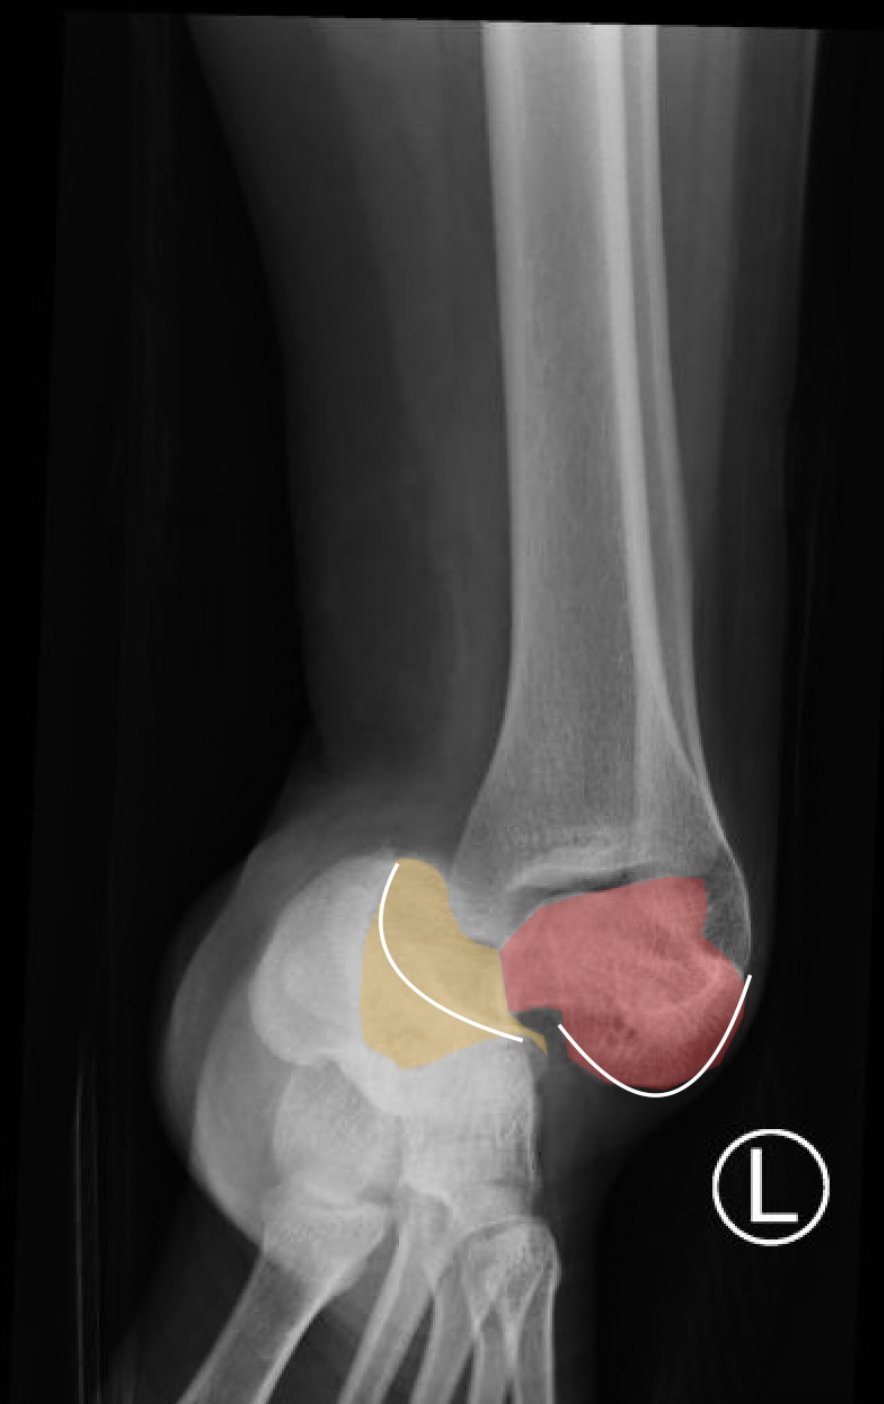

The X-rays were significant for a subtalar dislocation. The calcaneus (red) is laterally displaced with respect to the talar head (orange), and the white lines indicate the normal articular surface. Additionally, there was a talonavicular dislocation, as seen in the fourth image: the talus (green) and navicular bone (purple) overlapping suggests a dislocation. In a normally aligned foot, the boundaries of the two bones create a point of articulation.